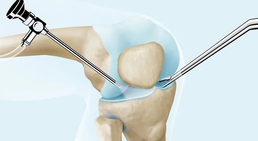

Kniearthroskopie

Die Kniearthroskopie ermöglicht eine detaillierte Untersuchung des Inneren des Kniegelenks. Sie wird häufig zur Diagnose und Behandlung von Knieerkrankungen...